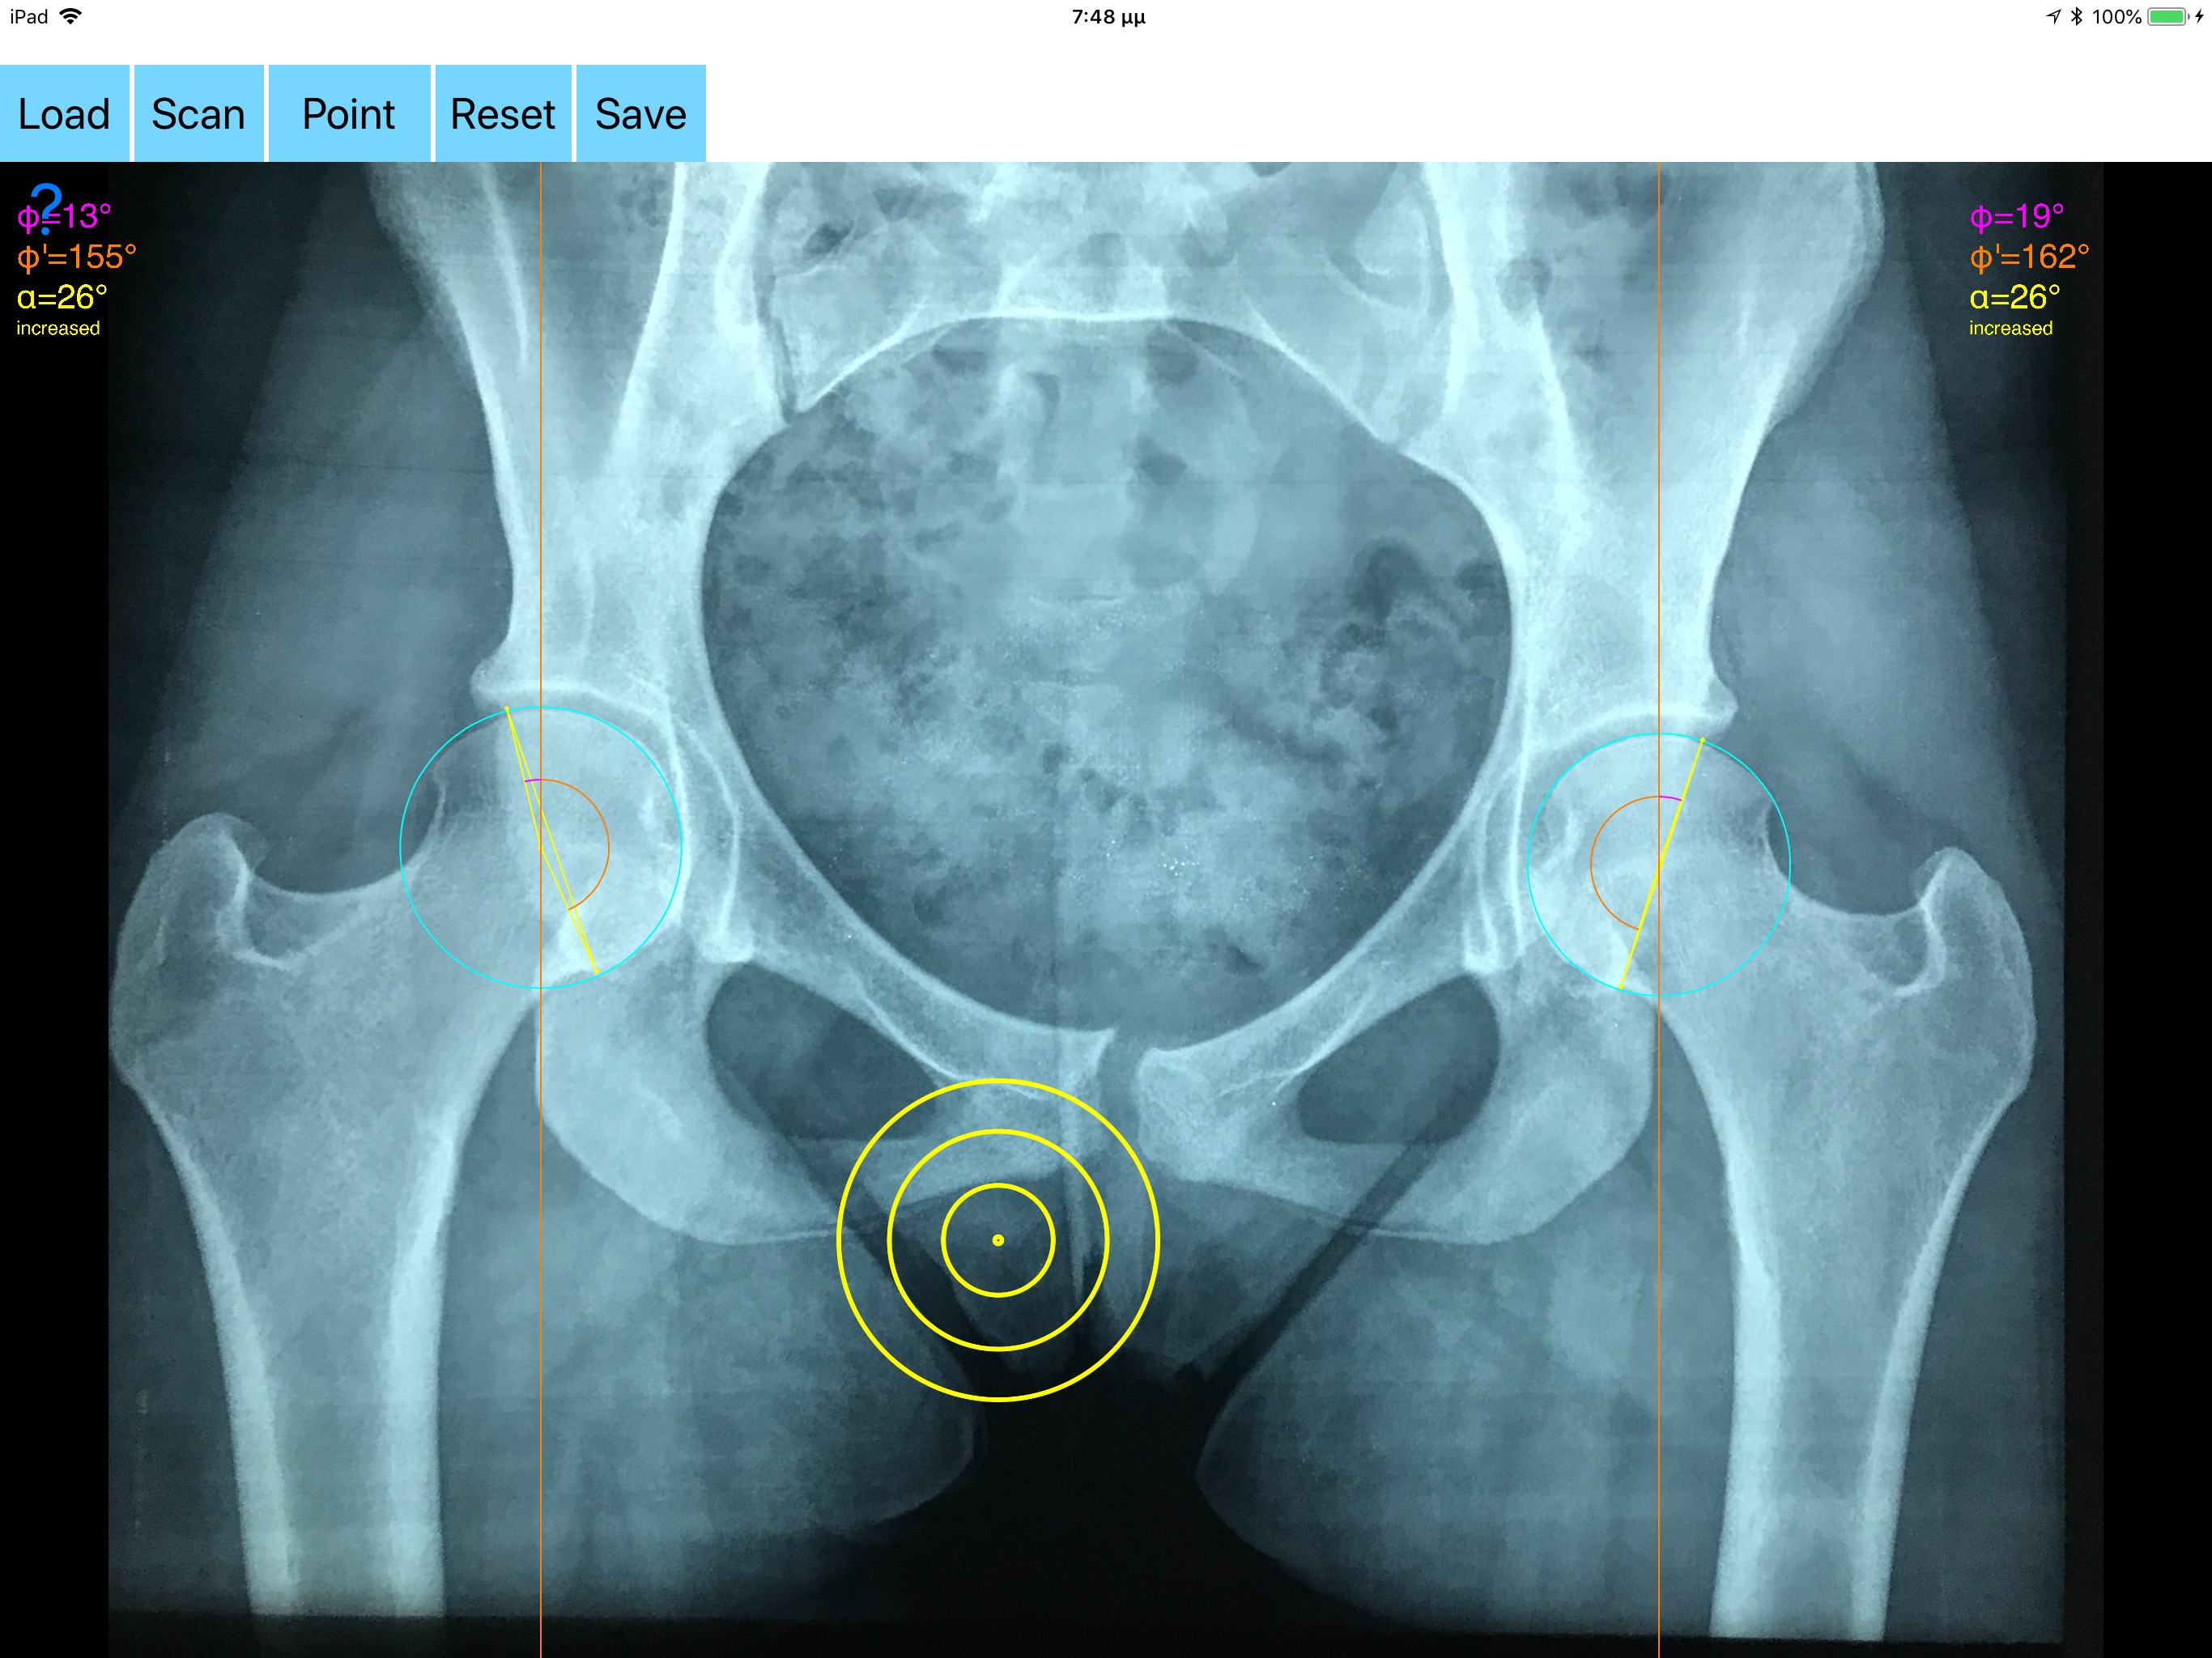

Acetabular version refers to the anteroposterior orientation of the acetabular opening relative to the true horizontal axis of the pelvis. The normal human acetabulum is anteverted in order to allow impingement free range of motion including flexion, adduction, and internal rotation. Abnormal acetabular version has been correlated with pathologic hip conditions including femoroacetabular impingement (FAI) and developmental hip dysplasia.The association between acetabular version and hip pain has been well established in recent years as a source of contributing to early hip osteoarthrosis and labral tears. Recognition and appropriate treatment of abnormal acetabular version is crucial to preventing irreversible damage to the hip Acetabular version is conventionally evaluated on CT scans but excessive radiation doses associated with routine use of computed tomography (CT). An objective radiographic tool which provides measurements comparable in accuracy to CT measurements has been developed by Dr. Hefti (Nomogram).Tedious and time-consuming calculation has to be done in simple X-rays in order to calculate the acetabular anteversion. The primary goal of this App is to help determine radiographic values of acetabular anteversion in a practice in a blink of an eye and avoiding CT scans. The App is medical software aimed for orthopaedic surgeons, providing tools that allow doctors to: -Securely import medical images directly from the camera or stored photos. -By marking certain points in a simple standard AP pelvic radiograph, geometric parameters are being calculated. The App computes the acetabular anteversion based on a pelvic AP radiograph. The angle of anteversion is calculated through the formula according to Heftis nomogram. The acetabular orientation (anteversion/retroversion) is determine by the app by the measurement of the angles between the center of the femoral head and the anterior (φ) and posterior (φ’) acetabular rim. Once you choose correctly the anterior and posterior acetabular rims the app calculates the acetabular anteversion based on nomogram. -The data are printed over to screen so each case can easily assessed -Save the planned images, for later review or consultation. Disclaimer. Regarding its plausibility app offers no diagnosis or treatment. App provide an early indication that further evaluation may be warranted by Speciality Doctor. Explicitly is announced that the apps are not for diagnosis. Clinical judgment and experience are required to properly use the software. App alone do not replace an M.D. or specialist. All information received from the App output must be reviewed before any attempted treatment. The software is not for primary image interpretation. Any influence to the operators in making decisions remains user own responsibility and experience. App does not dispense medical advice. Patient should seek a doctor’s advice in addition using the app and /or before making any medical decisions for themself. Never substitute or replace doctors advice or change treatment modalities based on any measured outcome. App indicated for assisting healthcare professionals for scientific and research reason. Clinical judgment and experience are required to properly use the app and further research and validation is pending in coming future. Reference Friz Hefti, Pediatric Orthopaedics in Practice, Chapter5 , Pelvis hips and thighs 5.3.2.1 Biomechanics of the hip-Book. Springer